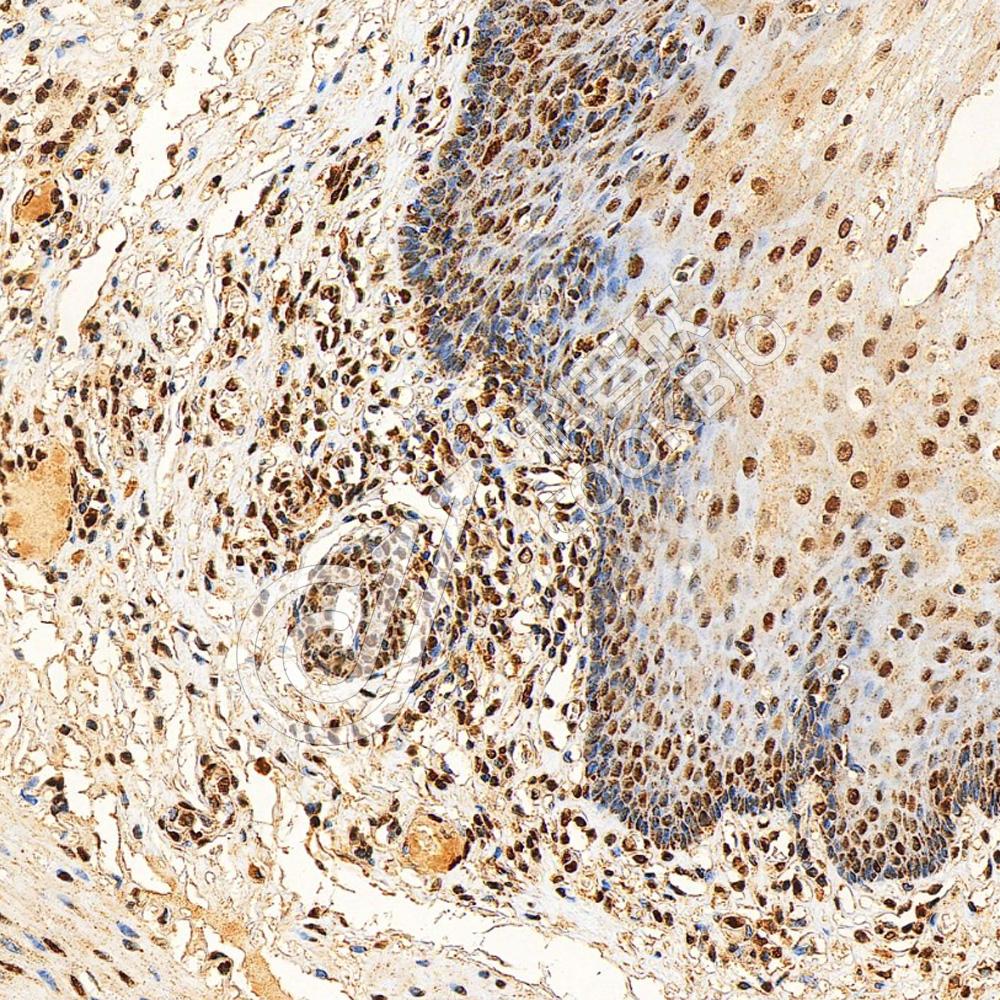

IHC检测Serum Response Factor SRF蛋白(货号 K1333144).

样品: 人胃癌, 4%多聚甲醛 (货号KSG1101) 固定12-24小时.

抗原修复: 柠檬酸抗原修复液(干粉, pH 6.0) (KSG1201), 98℃, 20分钟.

—抗: 1: 1800稀释, 4℃ 孵育过夜.

二抗: S-vision免疫组化多聚二抗(山羊抗兔),即用型 (货号KB3906), 室温孵育20分钟.